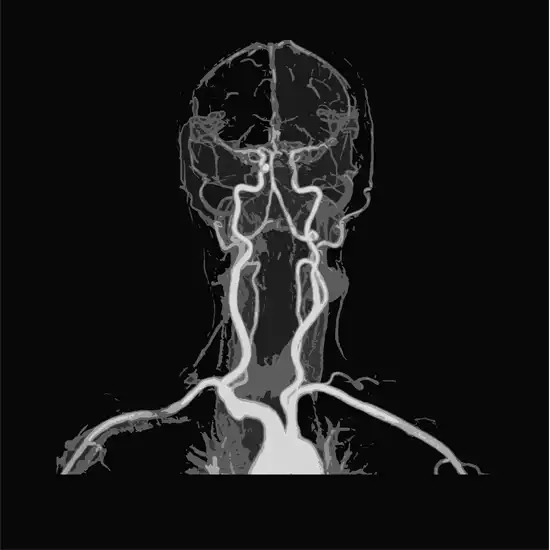

A brain MRI Scan is a diagnostic procedure that creates a picture of the brain bones (cranium), veins/arteries, cranial nerves, grey/white matter and surrounding soft tissues. Doctors use MRI angiography to diagnose and treat blood vessel-related diseases.

Magnetic resonance Angiography (MRA) is a powerful diagnostic technique which uses magnetic fields, radio frequency waves and a computer used to evaluate the blood vessels and help in identifying abnormalities.